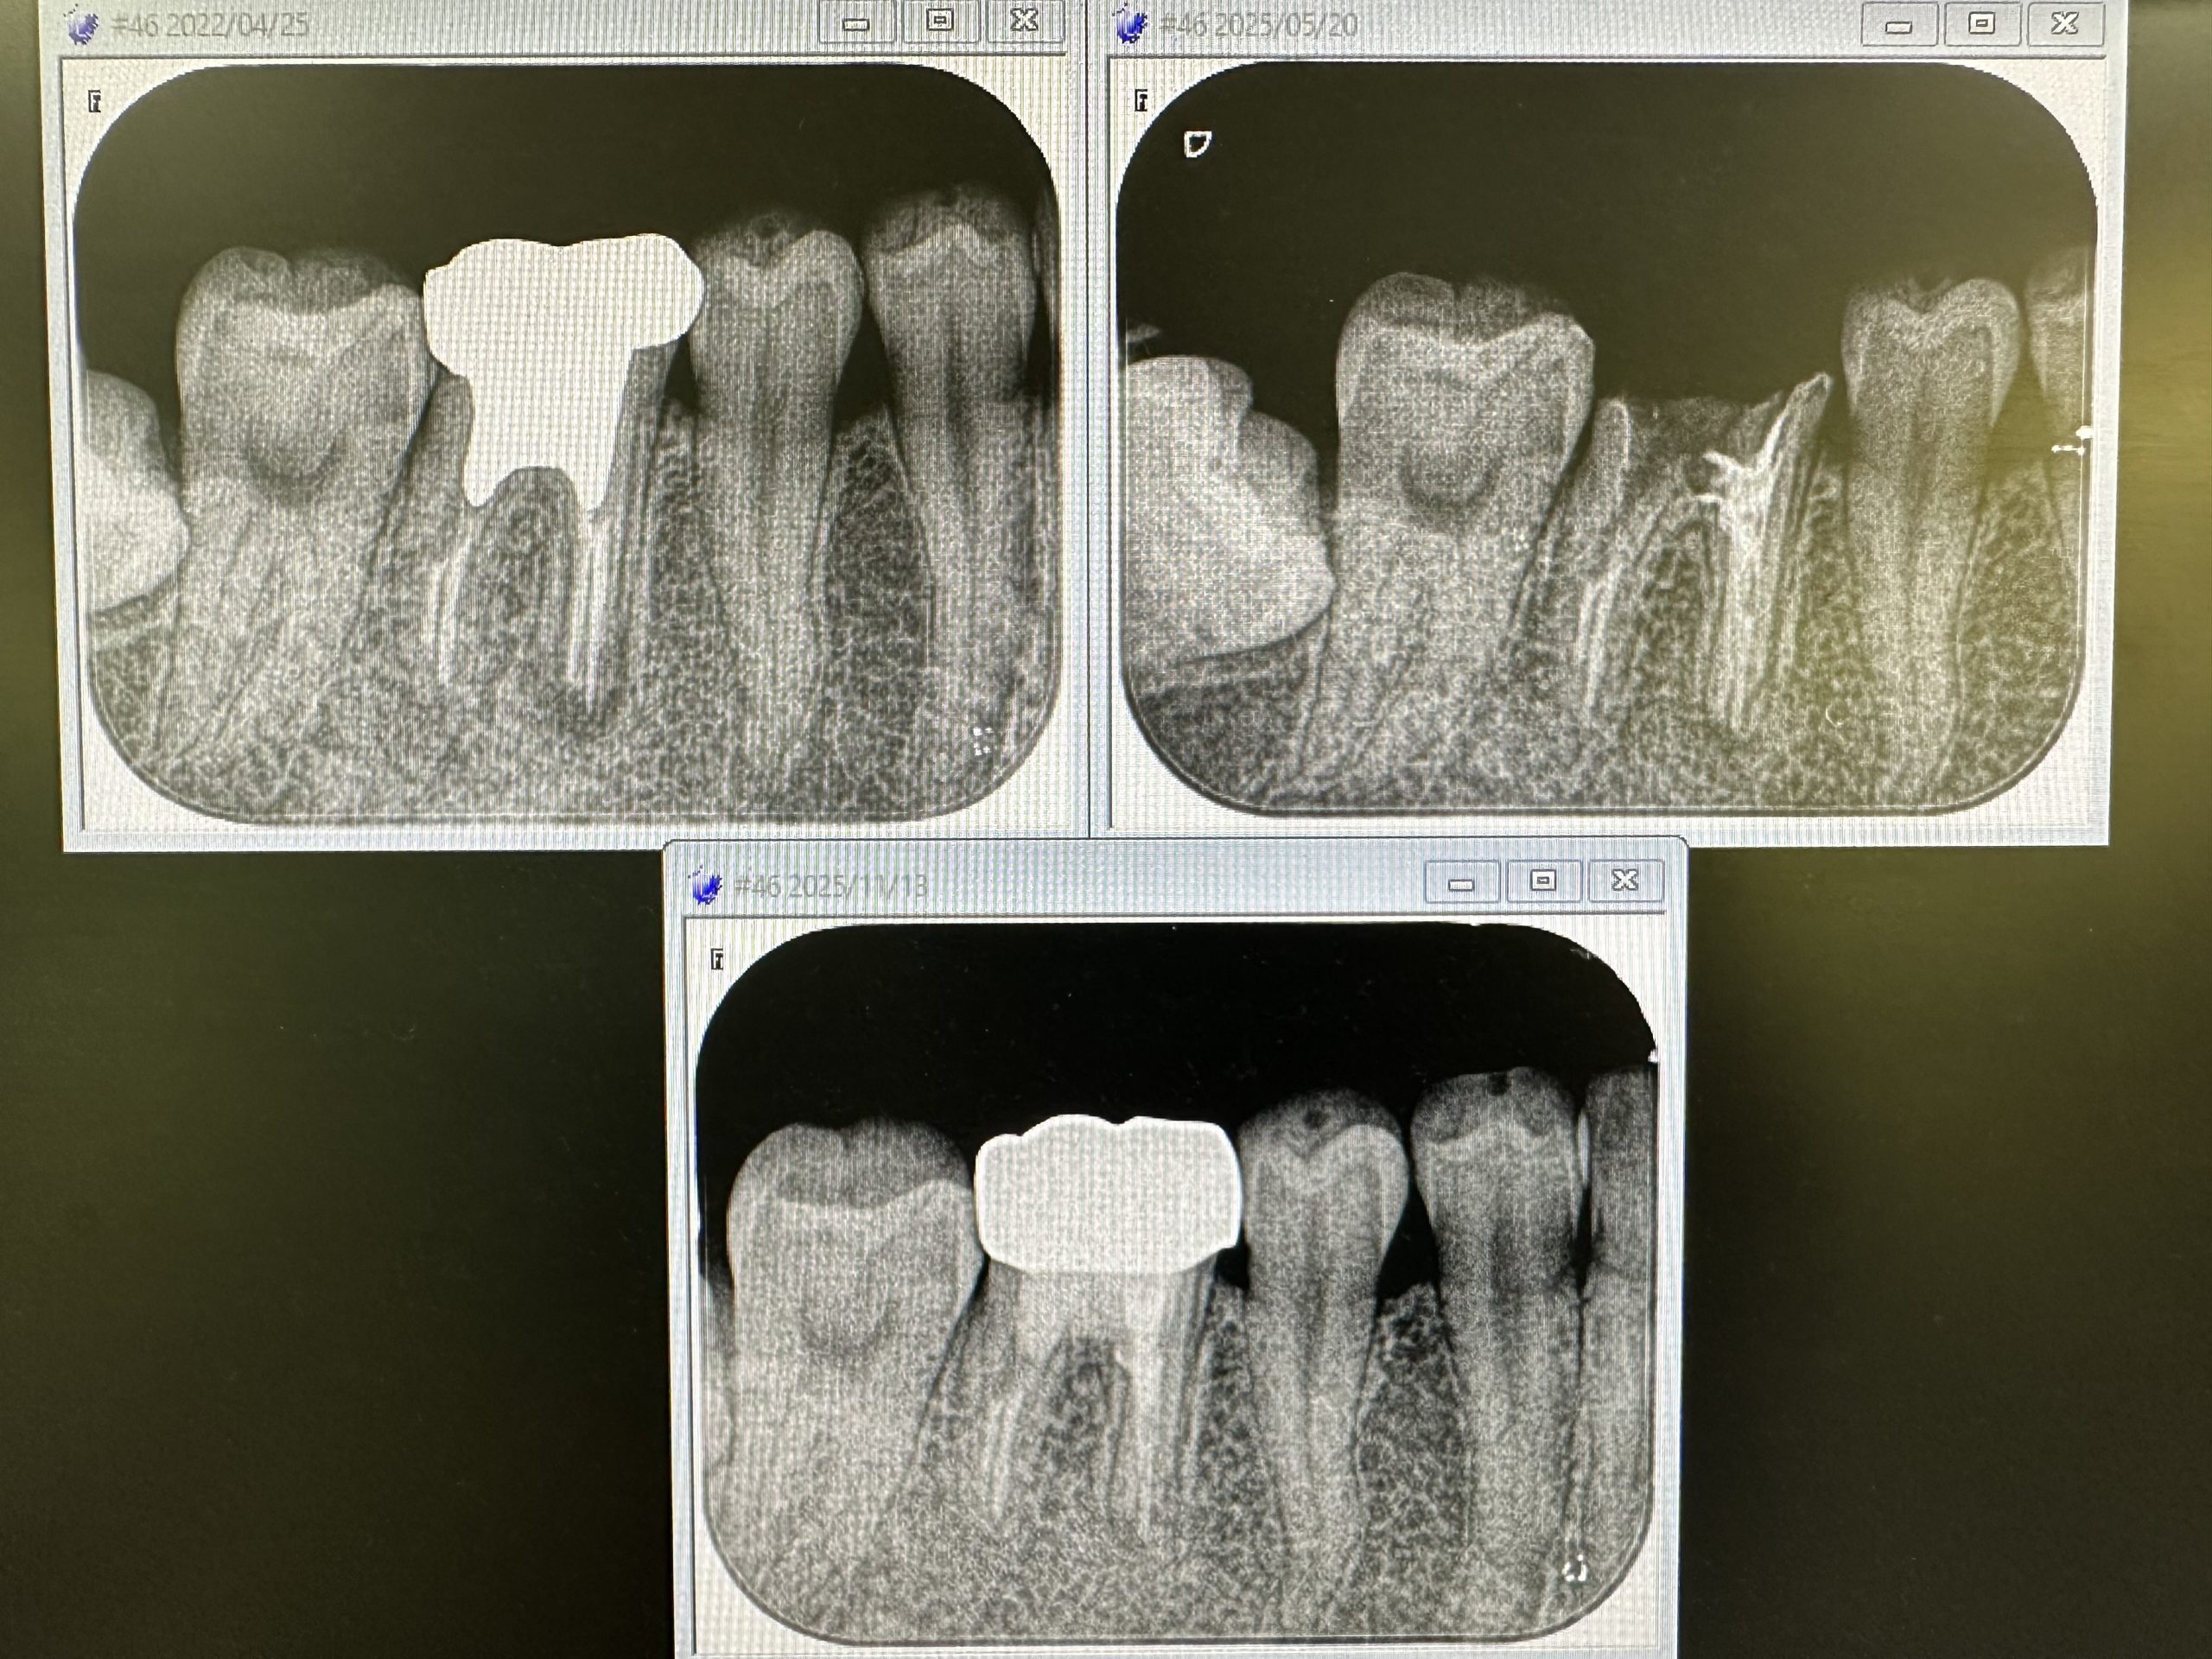

昨日忘れたが、若い娘の根管治療の経過

太い悪のメタルコア除去、病巣も半年でよく

縮小している、ジルコニアセット、更に半年後の定期検査が楽しみだ